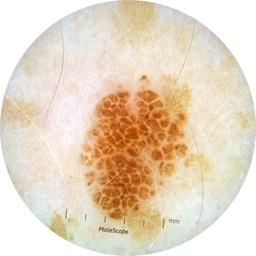

ISIC_3176953

Information

2135 x 2135

MEL-SELF Trial, https://www.sydney.edu.au/medicine-health/our-research/research-centres/melself-project.html

Clinical

Field Value

acquisition_day 410

age_approx 40

anatom_site_1 Head and neck

anatom_site_general head/neck

concomitant_biopsy False

diagnosis_1 Malignant

diagnosis_2 Malignant adnexal epithelial proliferations - Follicular

diagnosis_3 Basal cell carcinoma

diagnosis_confirm_type single image expert consensus

family_hx_mm False

fitzpatrick_skin_type I

image_manipulation instrument only

image_type dermoscopic

lesion_id IL_4059380

patient_id IP_8700330

personal_hx_mm True

sex female